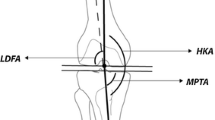

Coronal alignment of the lower limbs was determined by measuring inter-condylar (ICD) and inter-malleolar (IMD) distances with a calliper [8, 10]. Subjects stood in a relaxed, upright position with both feet pointing straight forward, hips and knees maximally extended and touching the medial femoral condyles or medial malleoli. Positive ICD-IMD values indicate increased intercondylar distance (varus alignment), while negative ICD-IMD values indicate increased intermalleolar distance (valgus alignment). All measurements were performed alternately by two trained examiners and repeated three times for each participant. The technical details of the measurement are described in Krajnc et al. [23].

In healthy children, the axes of the lower limbs change dynamically during the first and, to a lesser extent, the second decade of life [7, 8]. At birth, the coronal alignment of the knee is typically varus, but by the second year of life, varus begins to gradually rotate towards valgus, peaking between the ages of 3 and 5 years, followed by spontaneous correction by the age of 7 years to a physiological alignment of 1° valgus to 3° varus with ethnic and gender differences [7,8,9,10,11]. The development of bow legs (varus knee alignment above the physiological value of 3°) in late childhood and early teenage years is considered atypical, but in the majority of cases not pathological [3, 9, 12]. There are numerous factors that contribute to the development of lower limb varus, such as environmental conditions, sports activities, gender, obesity, metabolic disorders, vitamin D deficiency, etc. [9, 12].

Varus malalignment alters lower limb biomechanics by shifting the centre of the mechanical axis medially, which increases the load on the medial knee compartment, increasing the risk of early-onset degenerative joint disease [12, 16, 17]. In addition, bowed legs predispose athletes to various overuse injuries, patellofemoral pain syndrome, meniscal lesions and medial tibial syndrome [3, 17, 18]. It has been clearly demonstrated that participation in sports is associated with an increased incidence of varus knee alignment in young athletes compared to peers who do not participate in sports [3, 8, 17, 19,20,21]. This is particularly true for young football players, which is probably due to the specific loading patterns in football [3, 8, 17, 20, 21]. The influence of other sports, e.g. ice hockey, on axial alignment of the lower limbs is less well studied. Nevertheless, some studies reported a trend towards increased varus knee alignment in children participating in weight-bearing sports [15, 22].